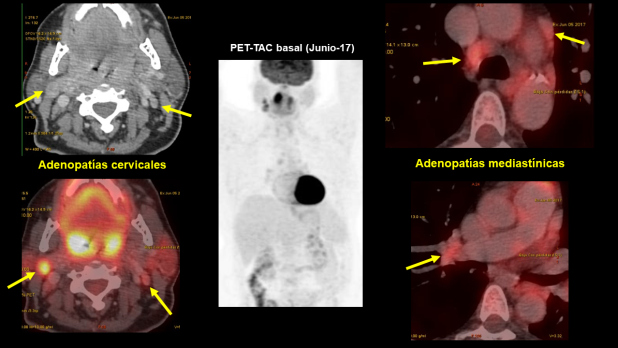

Un estudio PET-CT con FDG muestra (figs. 1 y 2):

Adenopatías con incremento de la actividad metabólica en las siguientes localizaciones:

Nivel II A derecho (SUV 10) de 18 x 23 mm.

Nivel II B izquierdo (SUV 3,2) de 11 x 4,6 mm.

Paratraqueal inferior derecha (SUV 5) de 12,7 x 10, mm.

Prevasculares (SUV 3.2) de 15 x 7 mm

Hiliar derecha (SUV 3,4) de 16 x 12 mm.